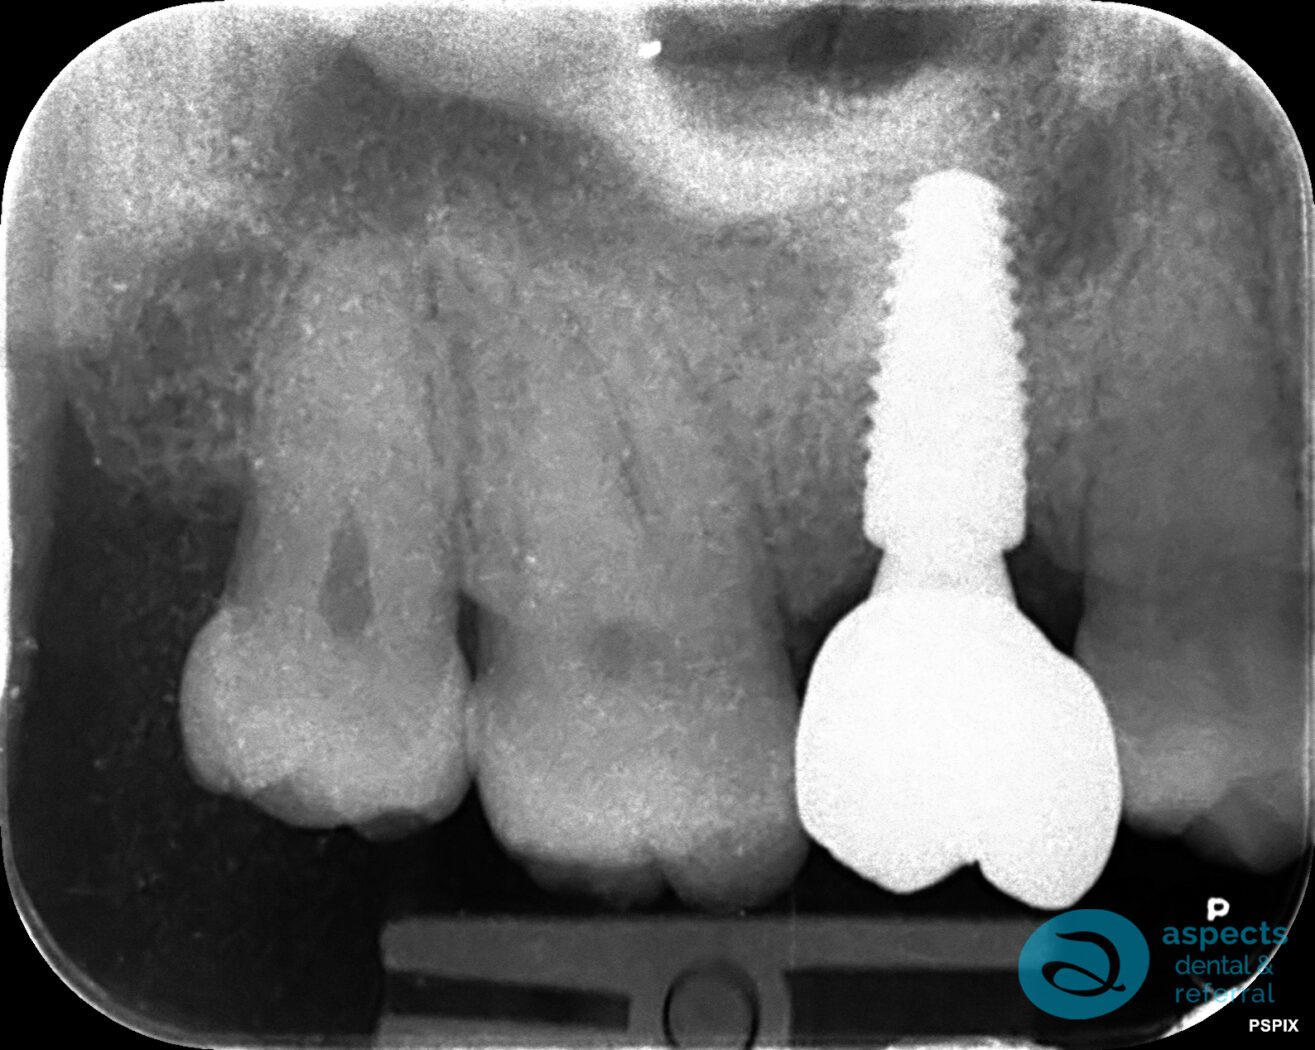

Following extraction, a sinus lift procedure was performed to augment the deficient bone volume and create adequate support for future Dental Implant Placement. After a successful healing period and radiographic confirmation of graft integration, a dental implant was placed in the augmented site.

After Dental Implant Xray